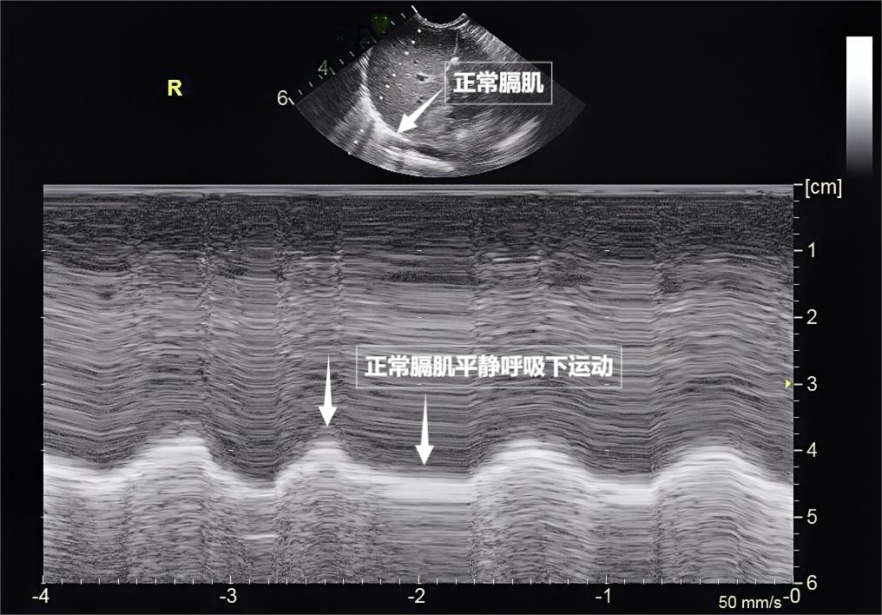

第三景:“呼吸的动力泵”的协同作战——呼吸肌肉

呼吸看似简单,实则是多组肌肉精密配合的“团体操”。肺部超声不仅能观察肺的形态,更能通过实时动态影像,“捕捉”这些呼吸肌的活动状态,为评估呼吸功能提供独特视角。膈肌是呼吸肌的“总指挥”,位于胸腔与腹腔之间。平静呼吸时,膈肌收缩下沉,胸腔容积扩大,空气自然吸入;舒张时,膈肌回升,肺部弹性回缩完成呼气。超声下可见膈肌呈光滑弧形,随呼吸规律上下移动(见下图)。肋间外肌则是“肋间隙的升降机”,收缩时上提肋骨,扩大胸腔前后径,辅助吸气。这对“黄金搭档”承担了日常呼吸70%以上的工作量,是维持呼吸的“主力军”。

▲图为正常膈肌超声表现